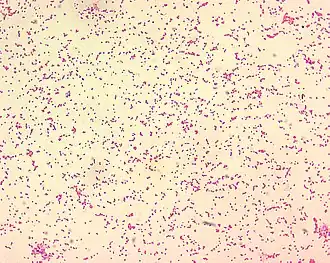

Brucella spp

Brucellose (bij mensen Maltakoorts) is een infectieziekte bij mensen en zoogdieren die wordt veroorzaakt door bacteriën uit het geslacht Brucella. In 1887 werd deze bacterie voor het eerst geïsoleerd door de Britse militair chirurg Sir David Bruce op Malta.

Het was de Amerikaanse [[Alice Catherine Evans]] (29 januari 1881- 5 september 1975) die voor het eerst de link legde tussen Maltakoorts en ziekte van Bang. Dat het drinken van koemelk besmet met Brucella Abortus tot gezondheidsproblemen zou zorgen bij mensen vond zij een interessant fenomeen. Ze ging daarom op onderzoek uit en vroeg Dr. Eichorn, hoofd van de afdeling pathologie of hij meer gevallen kende waarbij ogenschijnlijk gezonde dieren die bacteriën uitscheidden die mensen konden besmetten. Hij wees haar vervolgens op de Maltakoorts. Evans ontdekte dat de bacterie inderdaad staafvormig is, maar dat ze soms zo kort zijn dat ze er rond uit zien[9]. Deze bacterievorm, die noch kokken noch een bacil was, werd daarom coccobacillen genoemd. Toen Evans haar werk in 1918 publiceerde werd het met veel kritiek ontvangen, de link werd gezien als medische godslastering. Daarnaast was ze ook nog eens een vrouw en had ze geen PhD[10]. In 1920 zou haar werk bevestigd worden door Karl F. Meyer en collega's. Vanaf dat moment ging men de term brucellose hanteren ter ere van zijn eerste ontdekker David Bruce. In de vier jaar die daar op volgden kwamen dezelfde bevestigingen van tien andere onderzoekers uit zeven verschillende landen[9].